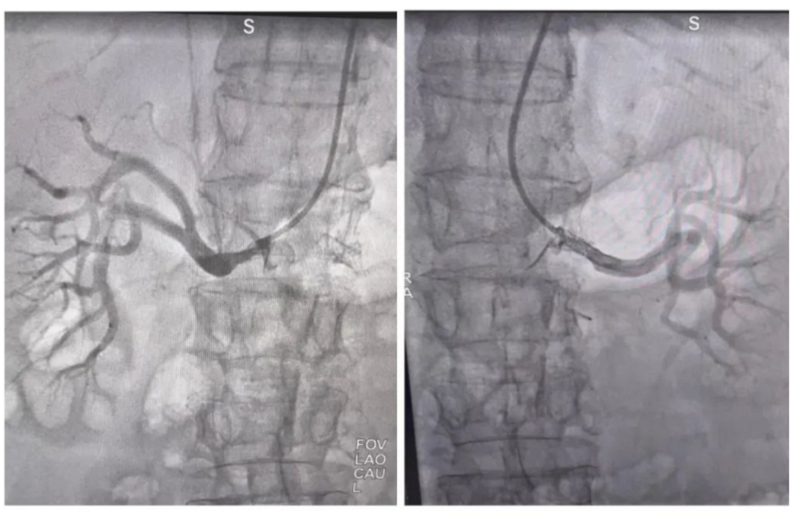

鲍阿姨术后复查肾动脉造影影像

万载县人民医院心血管科团队经过充分的讨论并且与家属商议后,决定在鲍阿姨的肾动脉狭窄处植入一枚支架。术后鲍阿姨恢复良好,血压也渐渐趋于平稳。